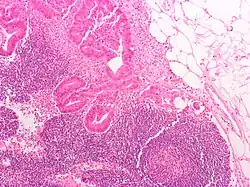

Local cancer in many parts of the body can cause lymph nodes to enlarge because of tumorous cells that have metastasised into the node.[36] Lymph node involvement is often a key part in the diagnosis and treatment of cancer, acting as "sentinels" of local disease, incorporated into TNM staging and other cancer staging systems. As part of the investigations or workup for cancer, lymph nodes may be imaged or even surgically removed. If removed, the lymph node will be stained and examined under a microscope by a pathologist to determine if there is evidence of cells that appear cancerous (i.e. have metastasized into the node). The staging of the cancer, and therefore the treatment approach and prognosis, is predicated on the presence of node metastases.